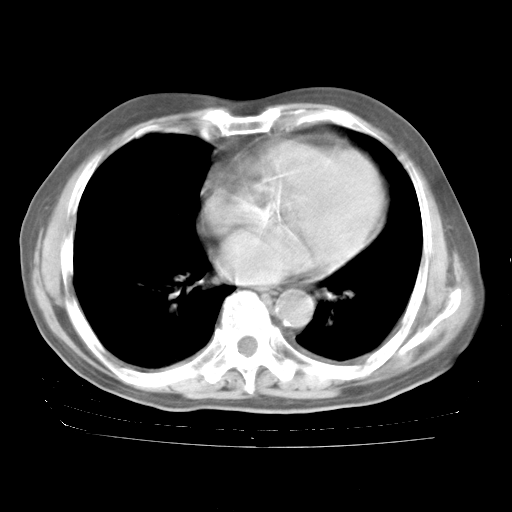

ECG:右心室增大

心脏超声检查:无右心室增大。